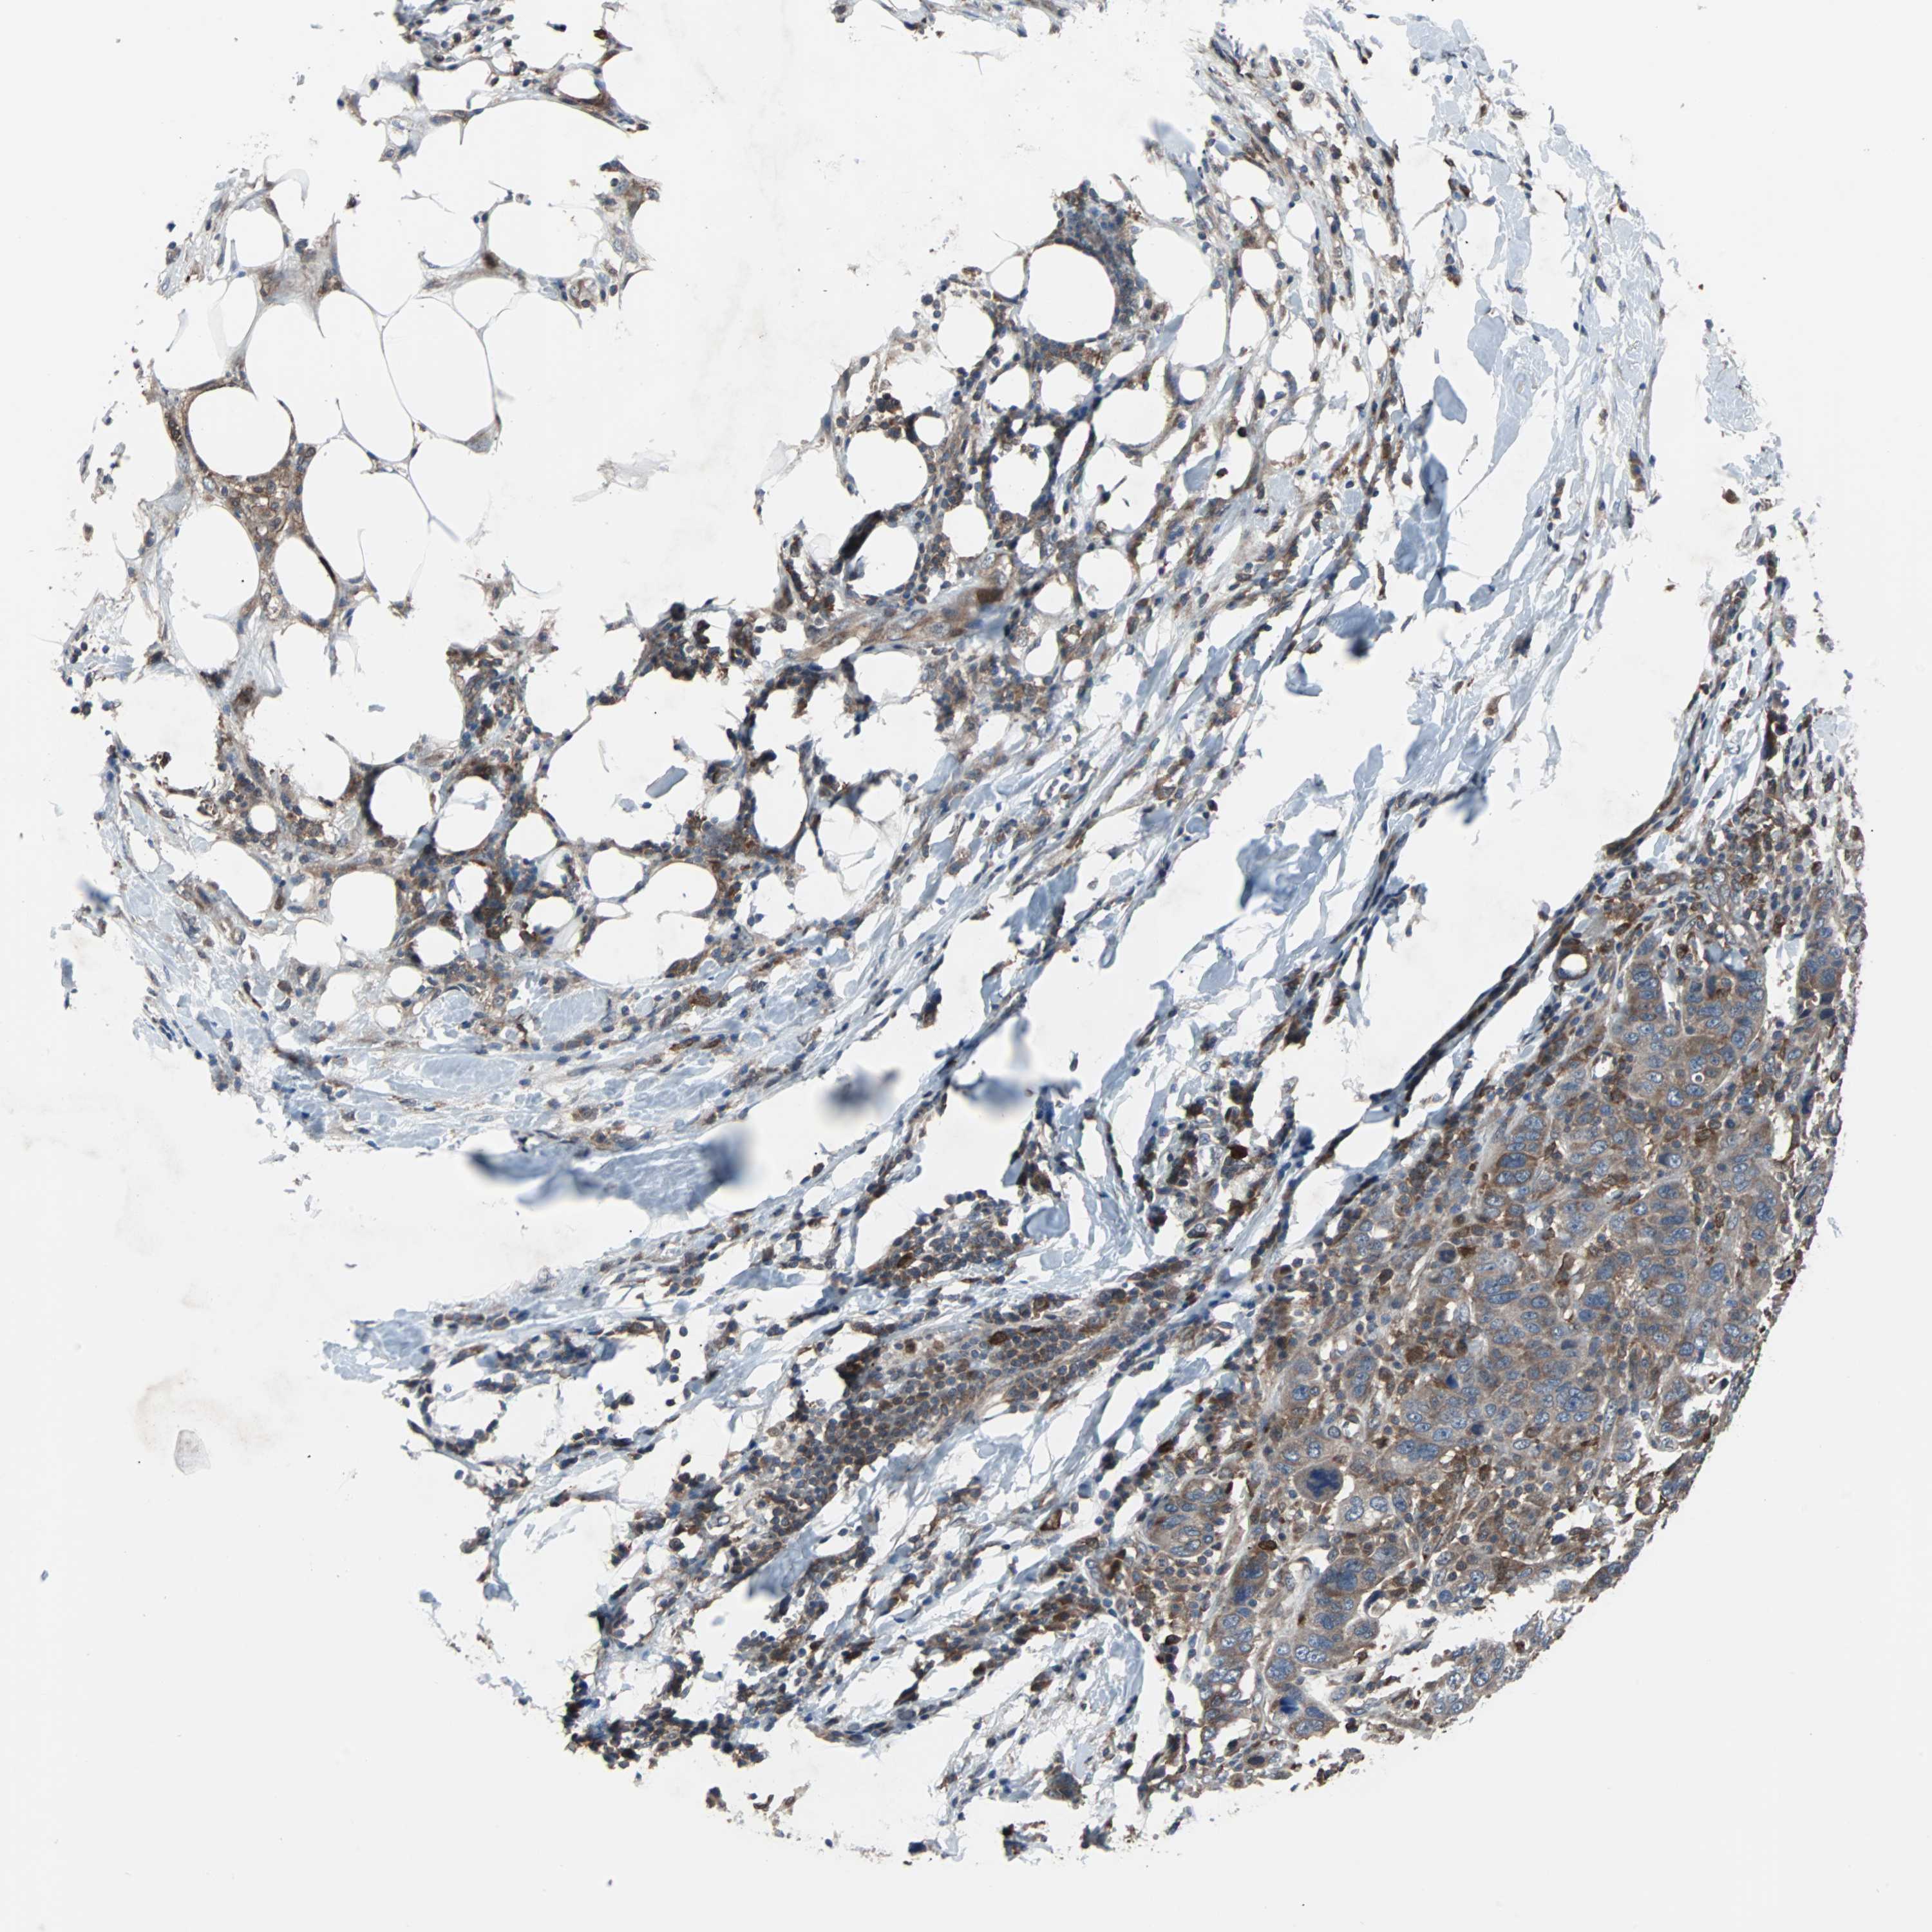

BRCA TCGA BRCA VALIDATION PROTEIN EXPRESSION